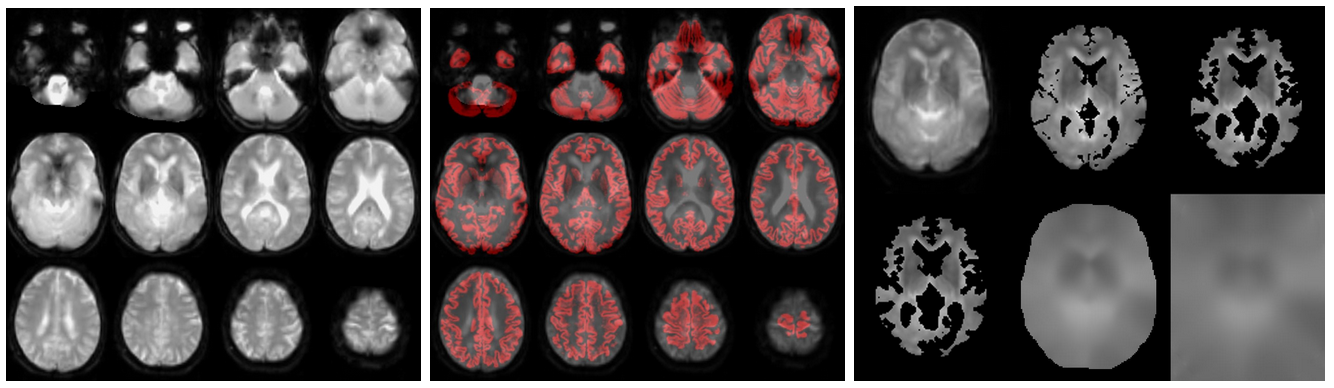

The structural module processes the anatomical (T1-weighted, T1w) images, to provide segmentations/partial volume (PV) maps and for spatial normalization to MNI space. Optionally, if FLAIR images exist, these are used to correct the white matter hyperintensities (WMH) on the T1w images. Check (from left to right):

• //Population/T1Check/Tra_Src_rT1_*.jpg for T1w quality, structural anomalies, normalization to MNI

• //Population/T1Check/Tra_Seg_rT1_*.jpg for T1w segmentation (WM segmentation in red)

If an M0 scan exists (from left to right):

• //Population/M0Check/Tra_noSmooth_M0_*_ASL*.jpg for the inspection of M0

• //Population/M0_Reg_ASL/M0_im_proc_*.jpg for processing of M0 into a smooth bias field (masking & smoothing). Verify that the mask correctly removes the CSF & extracranial signal, to avoid smoothing of this into the M0 bias field.